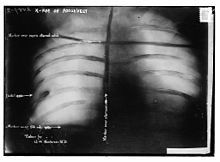

Assassination attempt

While Roosevelt was campaigning in Milwaukee, Wisconsin, on October 14, 1912, a saloonkeeper named John Schrank shot him, but the bullet lodged in his chest only after penetrating his steel eyeglass case and passing through a thick (50 pages) single-folded copy of the speech he was carrying in his jacket. Roosevelt, as an experienced hunter and anatomist, correctly concluded that since he was not coughing blood, the bullet had not completely penetrated the chest wall to his lung, and so declined suggestions he go to the hospital immediately. Instead, he delivered his scheduled speech with blood seeping into his shirt. He spoke for 90 minutes. His opening comments to the gathered crowd were, "Ladies and gentlemen, I don't know whether you fully understand that I have just been shot; but it takes more than that to kill a Bull Moose." Afterwards, probes and x-ray showed that the bullet had traversed three inches (76 mm) of tissue and lodged in Roosevelt's chest muscle but did not penetrate the pleura, and it would be more dangerous to attempt to remove the bullet than to leave it in place. Roosevelt carried it with him for the rest of his life.

Because of the bullet wound, Roosevelt was taken off the campaign trail in the final weeks of the race (which ended election day, November 5). Though the other two campaigners stopped their own campaigns in the week Roosevelt was in the hospital, they resumed it once he was released. The bullet lodged in his chest caused his chronic rheumatoid arthritis – which he had suffered from for years – to get worse and it soon prevented him from doing his daily stint of exercises; Roosevelt would soon become obese as well. Roosevelt, for many reasons, failed to move enough Republicans in his direction. He did win 4.1 million votes (27%), compared to Taft's 3.5 million (23%). However, Wilson's 6.3 million votes (42%) were enough to garner 435 electoral votes. Roosevelt had 88 electoral votes to Taft's 8 electoral votes. This meant that Taft became the only incumbent president to place third in a re-election bid. But Pennsylvania was Roosevelt's only eastern state; in the Midwest, he carried Michigan, Minnesota and South Dakota; in the West, California and Washington; he did not win any southern states.